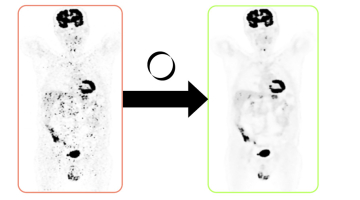

Hoe het Gentse softwarebedrijf dat allemaal concreet maakt, laten we liever uitleggen door co-founder Maarten Larmuseau. “Wij hebben software voor nucleaire geneeskunde ontwikkeld die ziekenhuizen toelaat om met behulp van minder radiotracer medische beeldvorming van dezelfde kwaliteit te genereren. Want hoewel de radioactieve vloeistof die gebruikt wordt heel beperkt is, blijft het in zekere zin schadelijk voor de patiënt. Hoewel minder radiotracer voor ruizige beeldkwaliteit zorgt, waardeert onze software die op.”

Momenteel krijgen patiënten gemiddeld 1 tot 2 millisievert (mSv) aan radioactieve vloeistof toegediend, aanzienlijk meer dan de dagelijkse natuurlijke stralingsdosis van 0,004 mSv. Hoewel deze dosis veilig is, blijft de straling niet zonder risico's. Maarten: “Als je minder tracer gebruikt, krijg je meer ruis in de beelden, wat kan leiden tot foutieve interpretaties. Onze software analyseert en verbetert die beelden zodat artsen dezelfde nauwkeurige diagnoses kunnen stellen.”